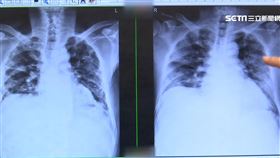

比癌症還奪命?他確診「菜瓜布肺」1年歿

你常忽略咳嗽、喘不過氣等肺部症狀嗎?小心與「肺纖維化...

聽診後背下肺葉發現「爆裂音」 當心

聽診趣健走活動 邀民眾認識菜瓜布肺 伸展手腳擺動身...

遠離肺阻塞! 這幾招教你提早發現

台大醫院內科部副主任王鶴健醫師說明,肺阻塞為慢性呼吸...

這個疾病名稱無癌字 存活期比癌症低

「其實我也不知道這(菜瓜布肺)是什麼玩意兒,後來知道...